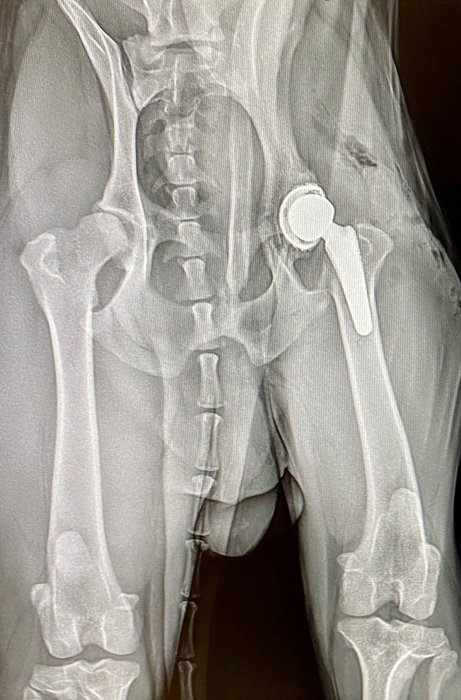

3. Was ist ein totaler Hüftgelenkersatz?

Bereits seit 1974 gibt es dieses vielfach erprobte und standardisierte Verfahren, bei dem ein fehlentwickeltes- oder stark geschädigtes Gelenk ersetzt wird. Alle Anteile des Gelenks werden hierbei durch synthetische/künstliche Materialen ersetzt. Dazu gehören die Beckenpfanne, der Oberschenkelkopf und der Oberschenkelhals. Aufgrund einer großen Vielfalt von anatomischen Gegebenheiten bei unseren tierischen Patienten, gibt es sehr unterschiedliche Implantattypen von denen manche in den Knochen geschraubt-, gehämmert oder einzementiert werden. Der Implantattyp wird bei der Voruntersuchung in jedem Fall einzeln festgelegt, um ein optimales Ergebnis zu erzielen.

Der Eingriff führt in 90-95% der Fälle zu einem sehr guten/guten Ergebnis und kann bereits nach wenigen Wochen zu einer langfristigen Schmerzfreiheit führen. Im Regelfall können Schmerzmittel und auch andere Medikamente abgesetzt und damit auch mögliche Nebenwirkungen verhindert werden. Hunde und Katzen erhalten ihre vollständige Mobilität und damit auch ihre Lebensqualität zurück.